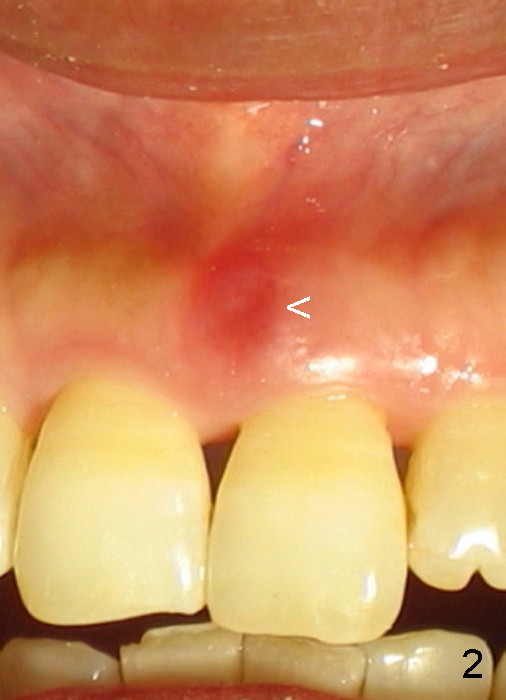

A 60-year-old lady had an abscess mesial to #9 six years ago (Fig.1,2 <), treated as a perio lesion by laser (Fig.3) and osseous surgery without bone graft (Fig.6, followed by CT exam revealing semi-circumferential bone loss (Fig.4,5). When the perio treatment failed, attention was paid to endo aspect (Fig.7-9). In fact the pulp was found to be vital when access to root canal therapy was made. As expected, the treatment failed again. The palatal fistula persisted. The infection was suspected to be a source of remote immediate implant site (#30). The tooth #9 was extracted. It appears that there is a semilunar crack line in the linguomesial root (Fig.12). When the socket healed 2 weeks post extraction (Fig.10), the #30 buccal defect was debrided with bone graft. There was no bone resorption 4 weeks post extraction (Fig.11); a 4.5x17 mm implant was placed (Fig.13-15). An immediate provisional was fabricated (Fig.16-18). Fig.19,20 were taken 3 months post implantation and 7 months post cementation, respectively. Dense bone forms around the implant coronally 4 years 5 months post cementation (Fig.21), while the gingiva is healthy palatally (Fig.22) and buccally (Fig.23).